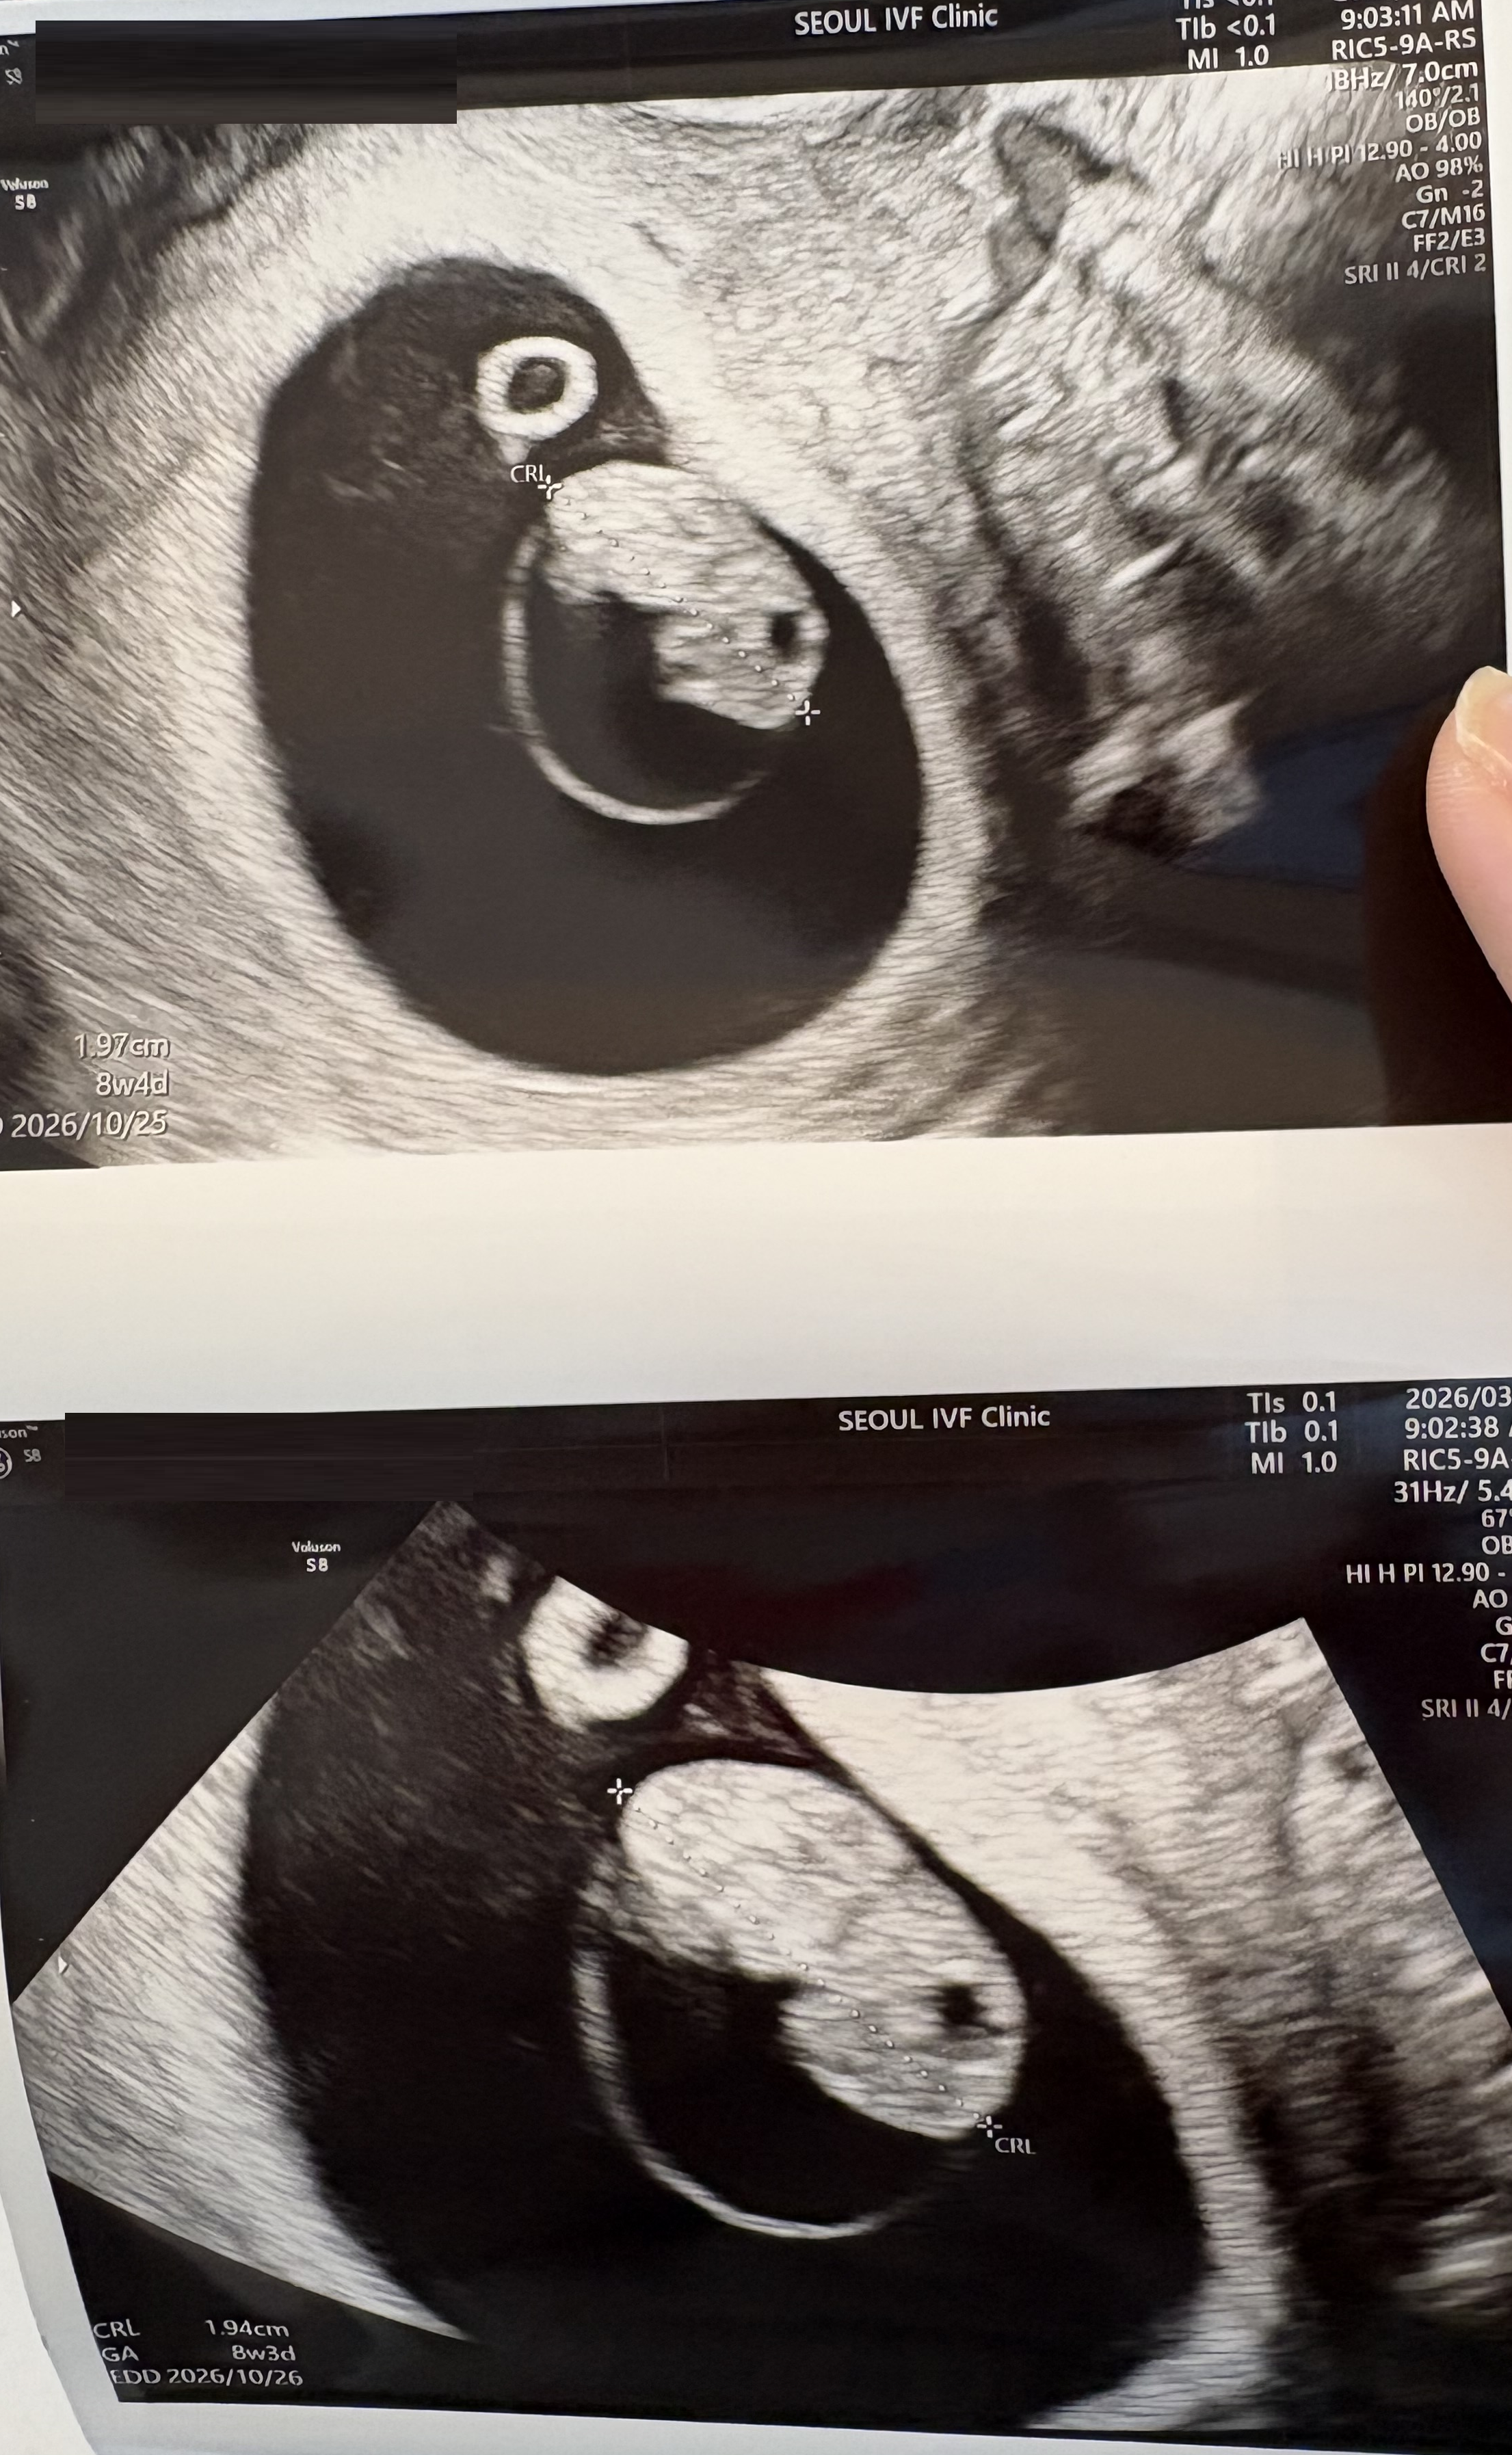

| 가슴 떨리는 임신 이야기를 공유해 주세요. | 나팔관조영검사, 인공수정, 시험관 1차와 2차까지 길고 힘든 시간을 거쳤지만 이예흔 원장님과 의료진의 도움으로 소중한 아이를 만나게 되었습니다. |